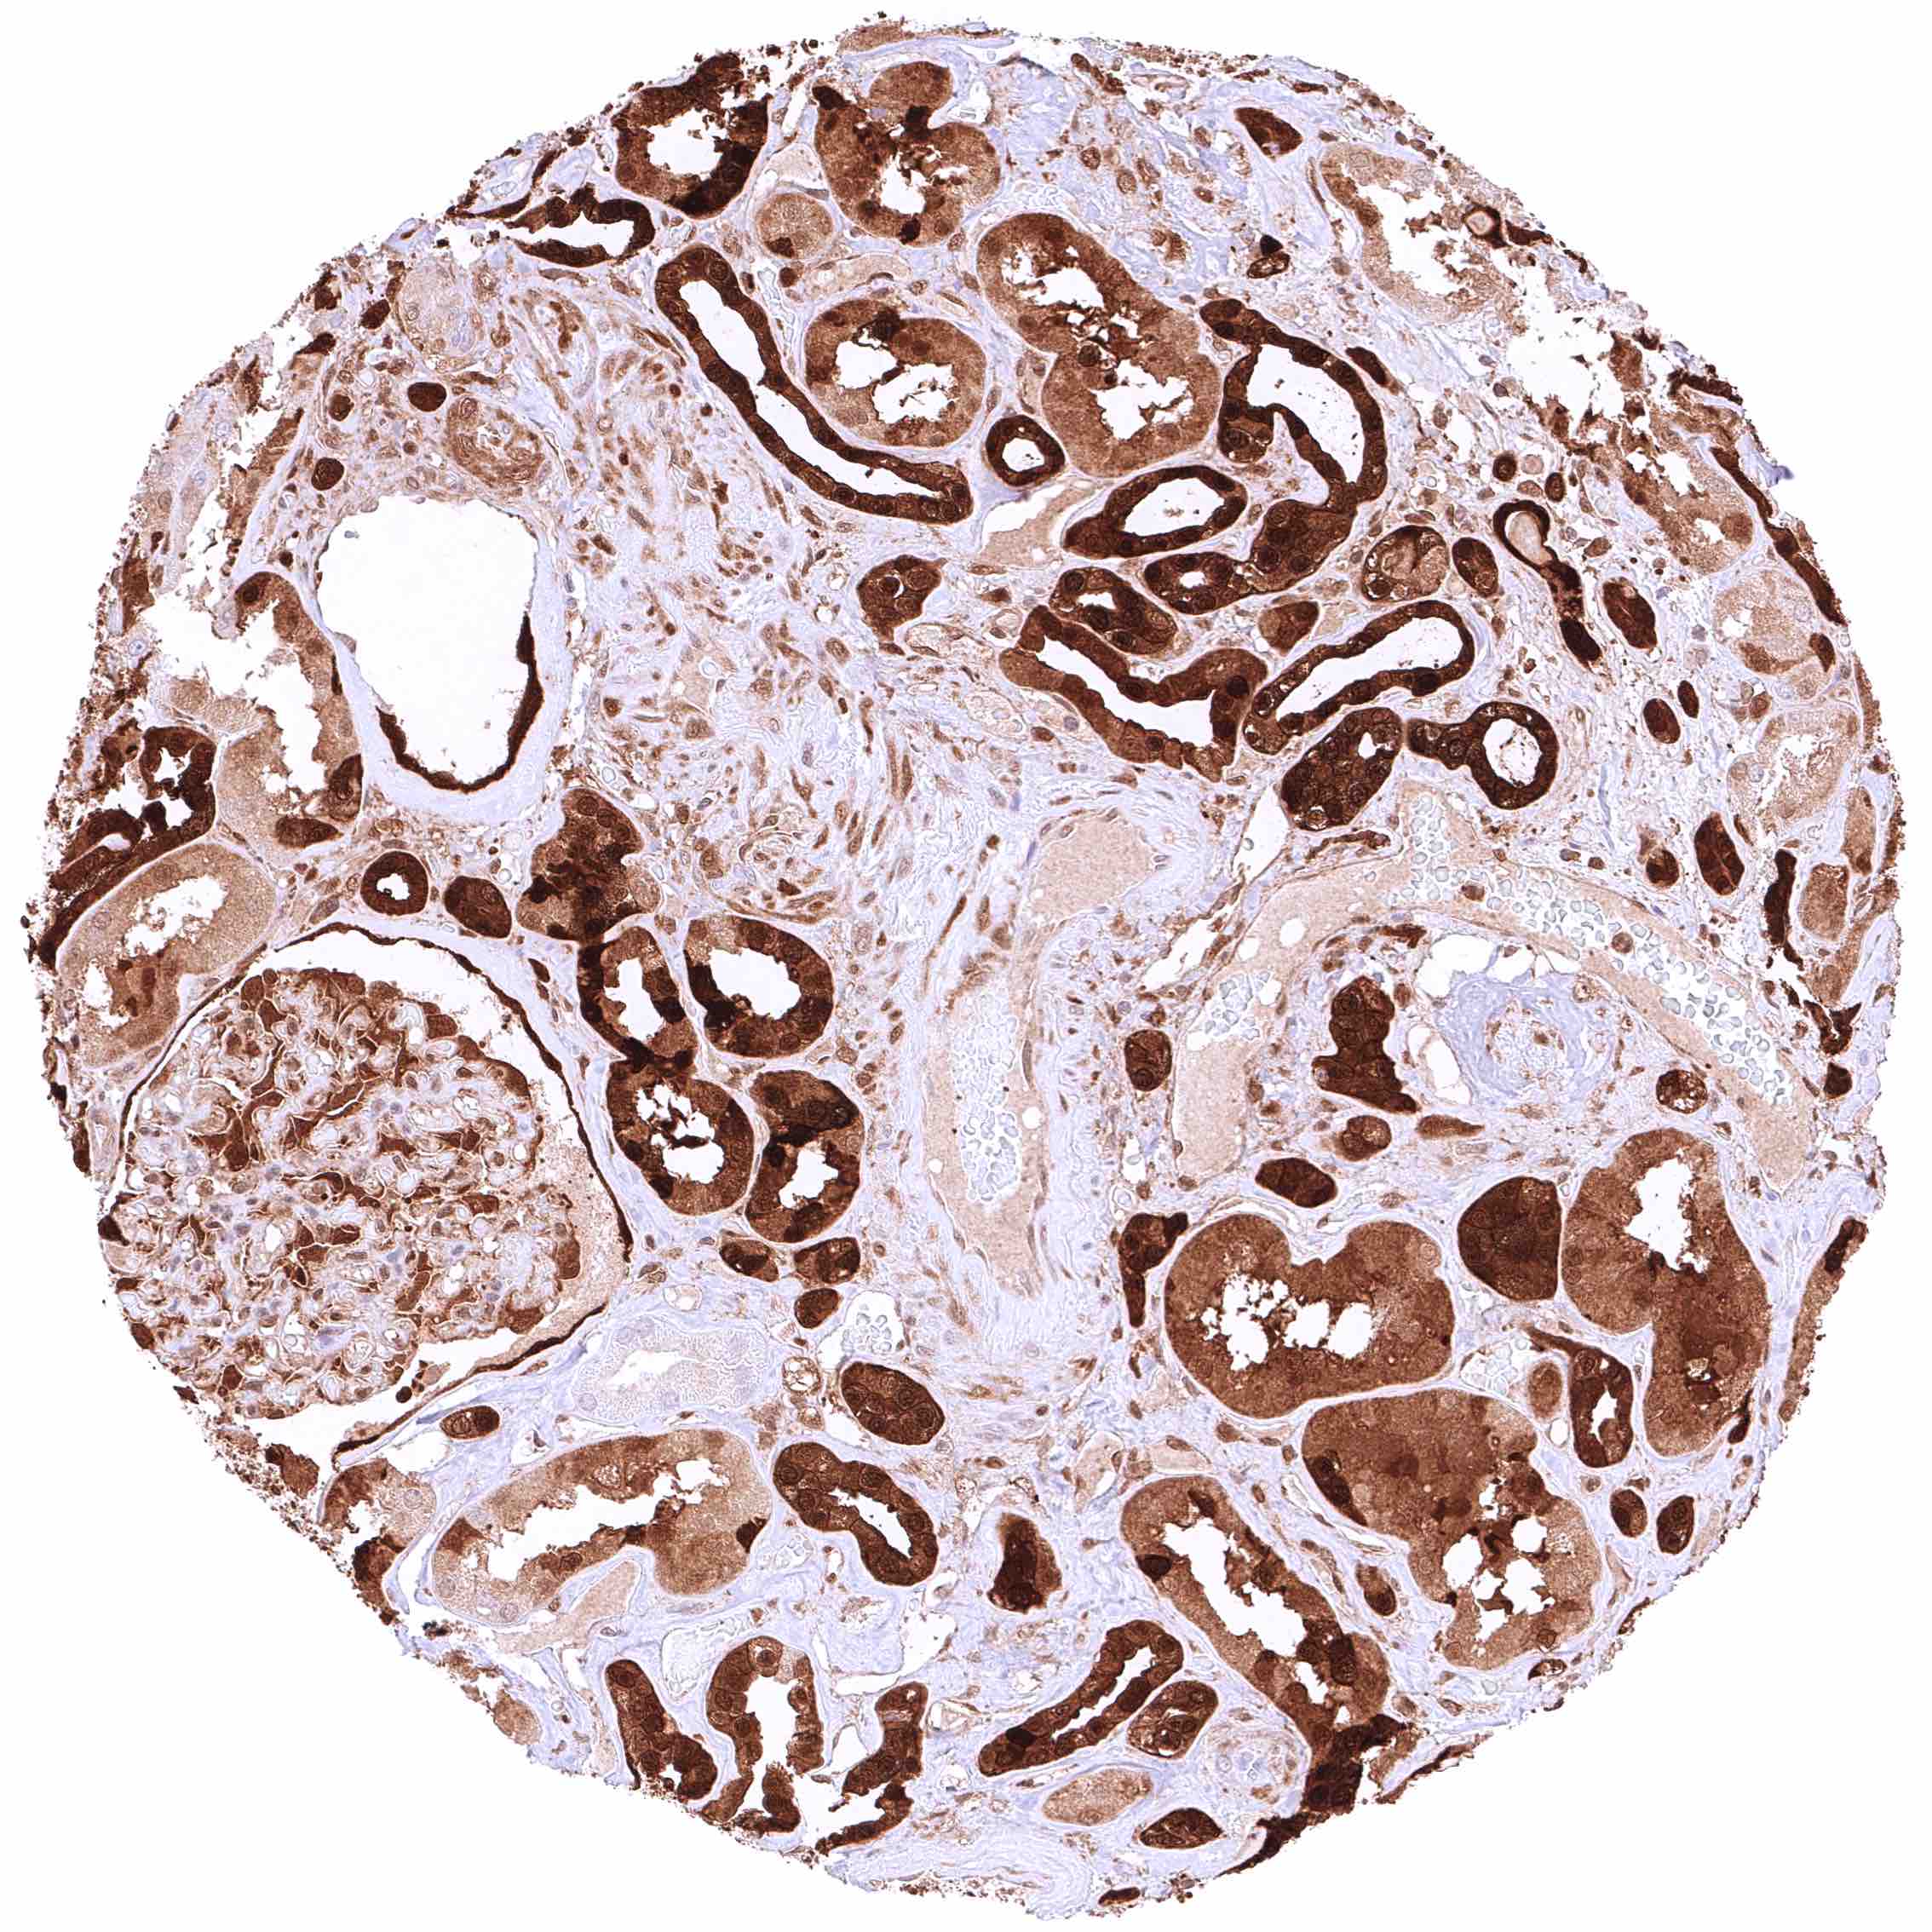

Kidney, cortex – GSTP1 staining is intense in distal tubuli, collecting ducts, and in the parietal layer of the capsule of Bowman but “only” moderate in proximal tubuli in this sample.

Kidney, cortex – GSTP1 staining is strong in distal tubuli, collecting ducts, and in the parietal layer of the capsule of Bowman but weak or absent in proximal tubuli in this sample.

Kidney, medulla – Strong GSTP1 staining in collecting ducts.